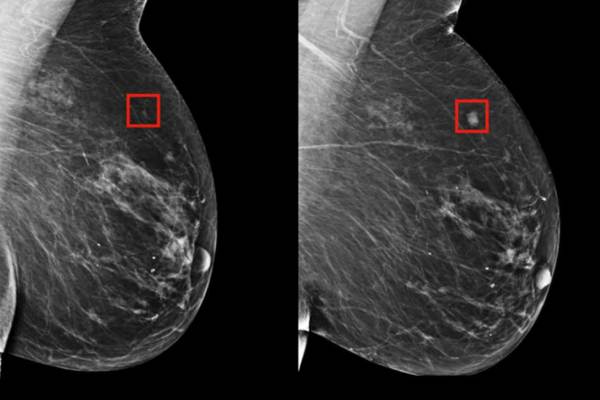

Hallo Mädchen! Es fühlt sich nicht so an, als würden wir 2018 ein halbes Jahr lang durchmachen. In Kürze im Oktober feiern wir immer den Tag des Brustkrebs. In meinem Blog möchte ich diesmal die Brustkrebsversorgung diskutieren und wie man den richtigen BH auswählt. Solche Dinge sollten nicht gelagert oder leise oder als peinlich angesehen…